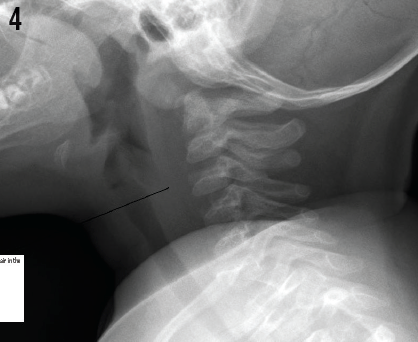

Cynthia H. Ho, MD; Erin G. Newman, MD; Cynthia L. Stotts, DO

A 12-year-old girl was emergently transported emergently by helicopter to the emergency department 1 hour after having sustained a rattlesnake bite to her left foot while she had been camping in Southern...